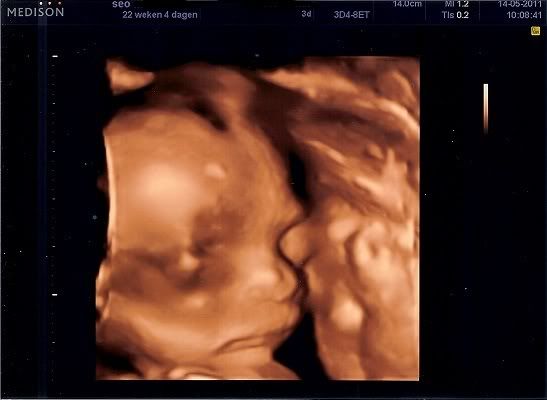

Afgelopen zaterdag hebben we eindelijk onze 20 weken echo gehad! En we zijn erg opgelucht en ontzettend blij, want alles was goed met onze kleine!! De echoscopiste was ontzettend leuk. We kregen zelfs een 3D echo erbij! En ze heeft een paar leuke foto's voor ons afgedrukt op echt fotopapier. We kregen zelfs een sleutelhanger met een klein 3D fotootje erin mee. Wat een ontzettend lief gebaar.

De echo's: